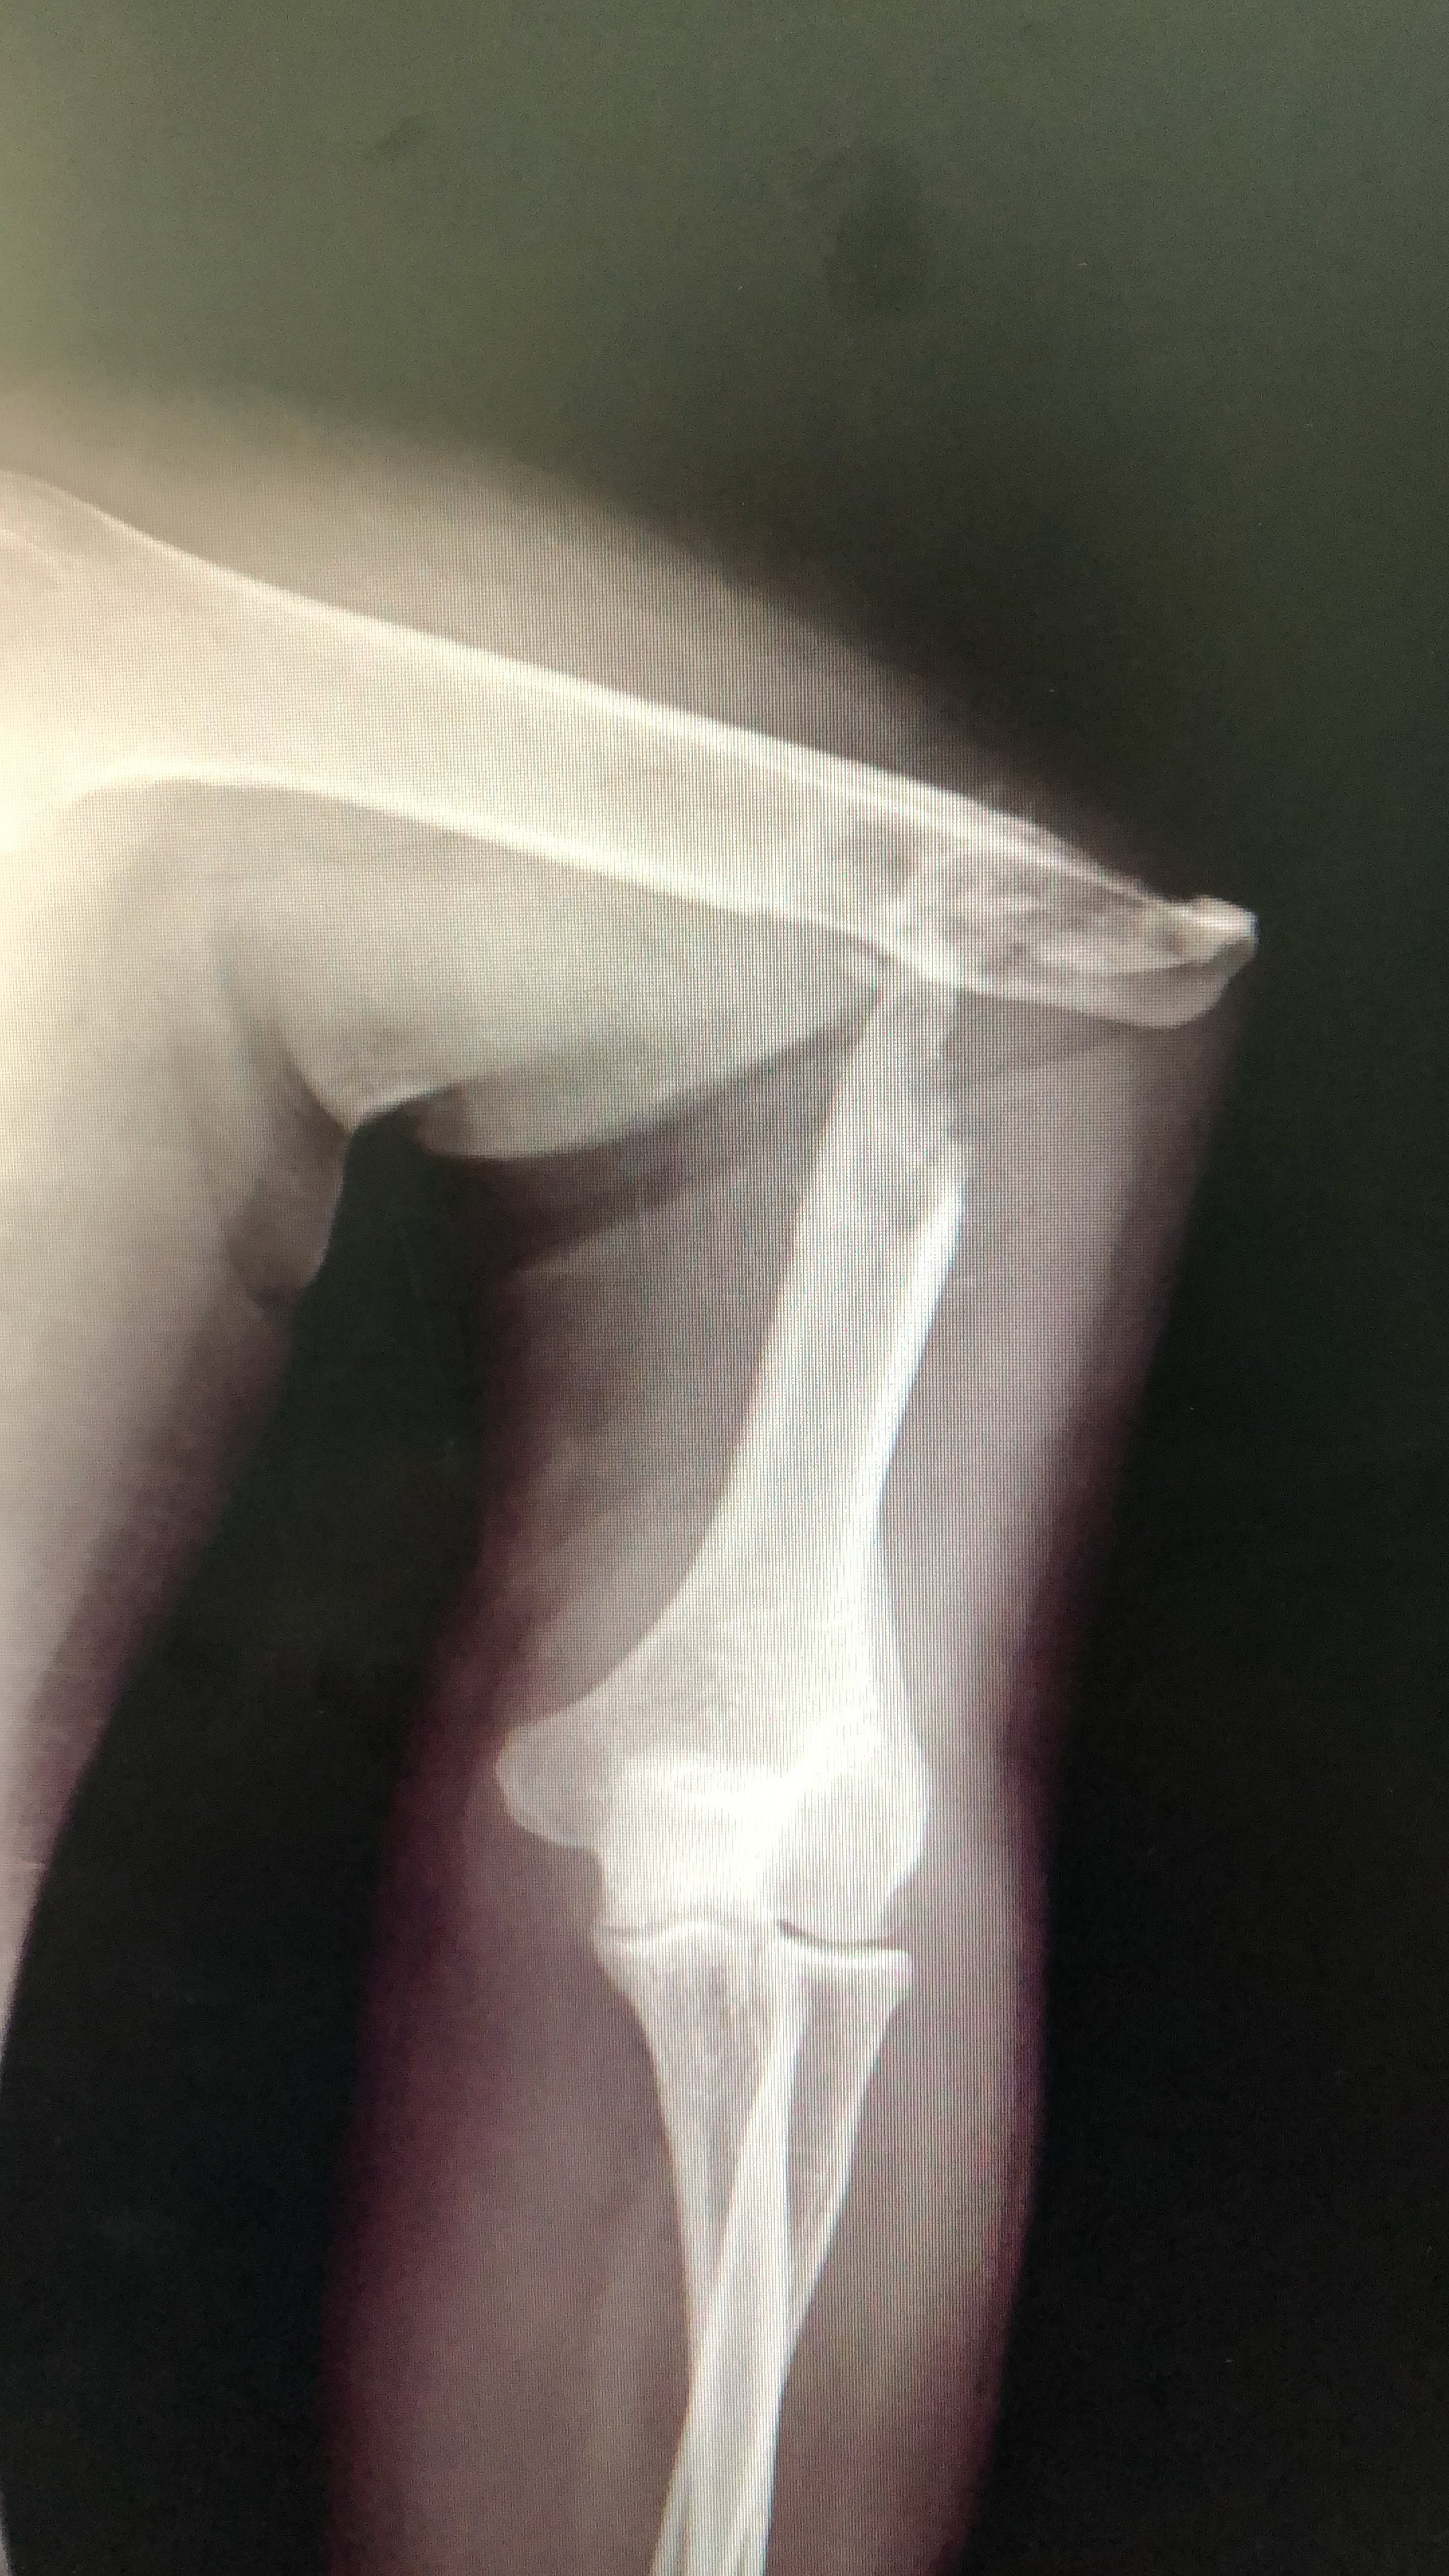

Como no podía ser de otra manera porque nos pasa siempre, nos hemos enfrentado a cirugía de alta complejidad, pseudoartrosis de húmero, fémur y tibia en adultos, así como  fracturas complejas.

Una cosa queda clara, los “masajes tradicionales cameruneses“ no son efectivos en el tratamiento de las fracturas de cualquier hueso, tanto en niños como en adultos y conducen inevitablemente a pseudoartrosis  muy difíciles de tratar.

La Dra. Zorita que viajaba por primera vez a nuestro Hospital en Dschang, ha visto patologías que en nuestro medio habitual en Europa son impensables. En la fotografía aparece junto a una paciente a la que le colocó un fijador externo por una fractura conminuta de pilón tibial abierta grado III B. También el Dr Soriano y el Dr Sotillo, que también era su primer viaje, pudieron actuar directamente en intervenciones que ya son muy raras para nosotros en el primer mundo.